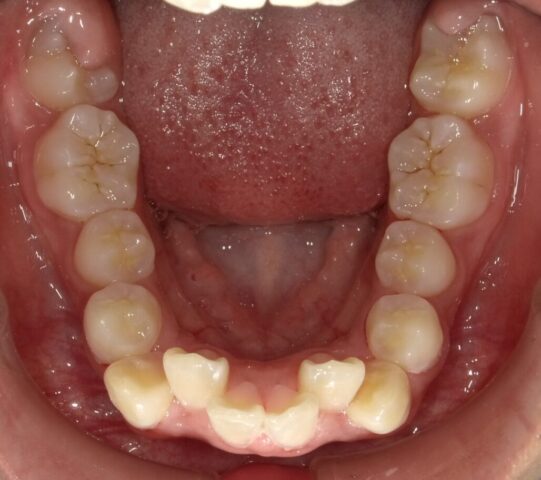

全て永久歯になりました。

あとは12歳臼歯を待ちます。

2023年12月(12歳2ヶ月)

12歳臼歯生え始めました。

しっかり出るまで経過を診ます。

2024年6月(12歳8ヶ月)

永久歯揃いました。

本人のやる気がでたら

2段階目スタートします。